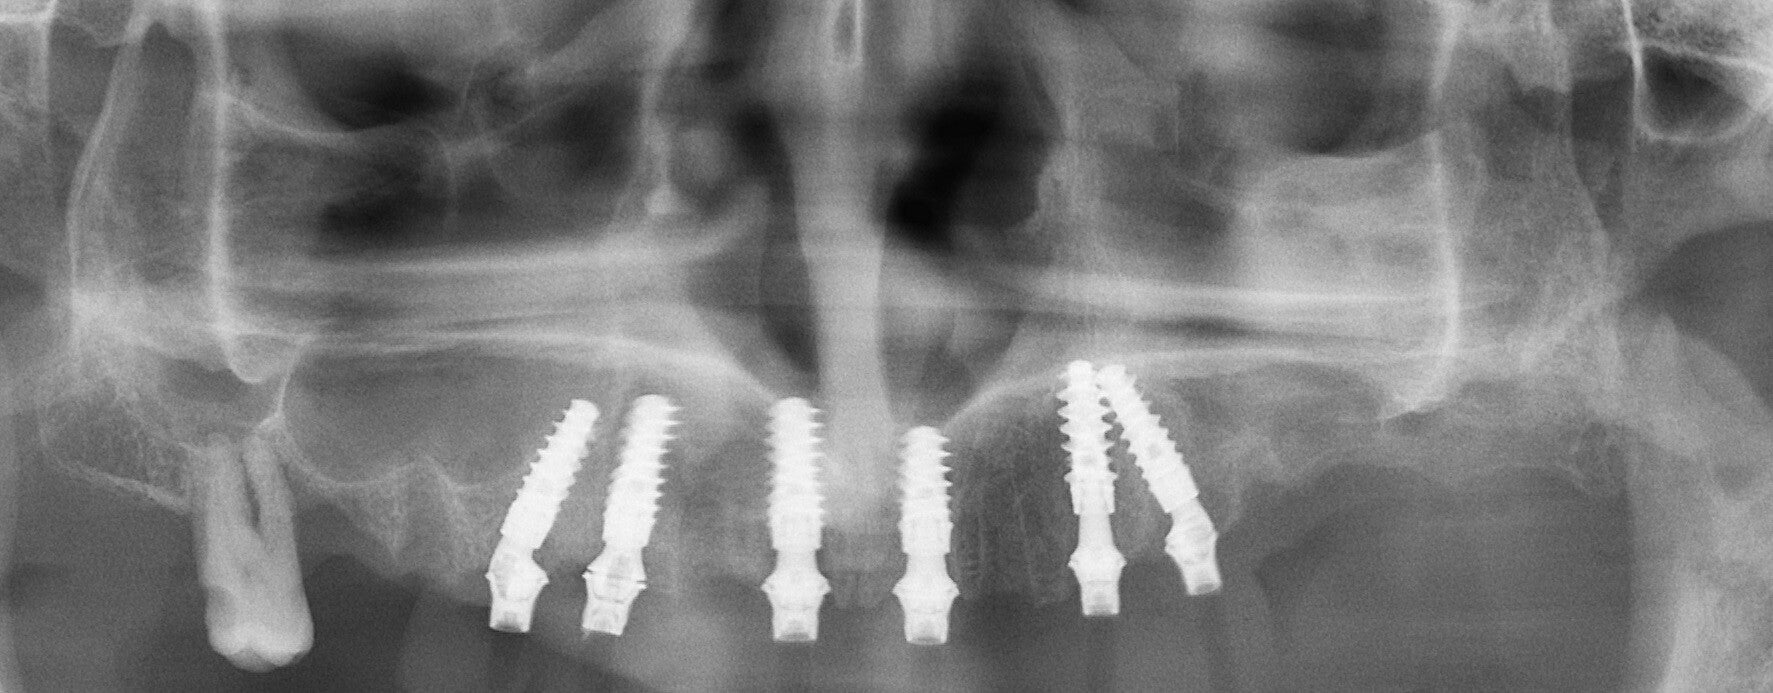

Rehabilitación de atrofias severas tanto maxilares como mandibulares mediante Implantes Cigomáticos e Implantes Personalizados Subperiósticos